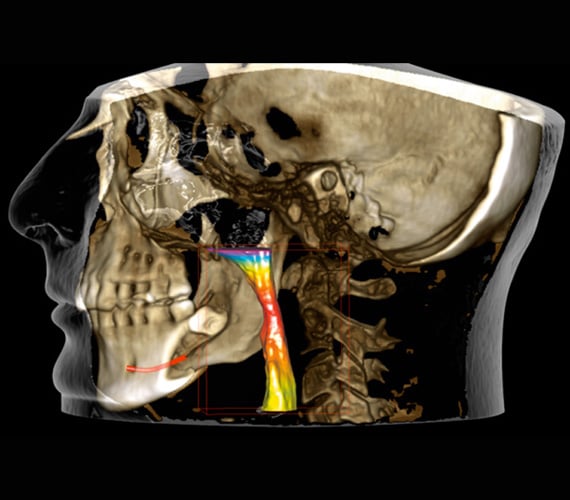

Airways are segmented with a few simple clicks in Romexis. The software automatically calculates the volume and minimal area and visualises the patient’s airways with vibrant colours. Our Planmeca Ultra Low Dose™ CBCT imaging protocol is also an optimal choice for examining airways, as it allows lowering the patient dose significantly without a statistical reduction in diagnostic image quality.